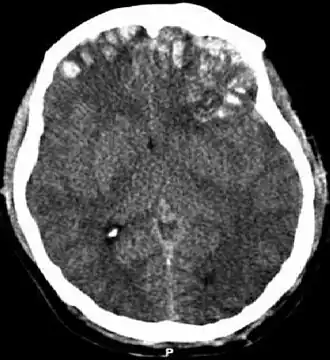

Scanner d'un traumatisme crânien.

Le scanner cérébral permet de voir l'étendue des lésions : présence d'une fracture, taille et localisation d'un hématome, conséquences sur les ventricules cérébraux, présence ou non d'un œdème cérébral. Une admission en unité de réanimation ou en soins intensifs de neurochirurgie est nécessaire. L'utilisation systématique d'une perfusion hypertonique dans le but de limiter l'œdème cérébrale a une efficacité discutée[22], de même qu'une ventilation hyperoxique (avec plus d'oxygène que de besoin)[23]. Toutefois, la mise sous ventilation artificielle est très souvent nécessaire. L'intérêt de la mise sous hypothermie est également incertain[23].